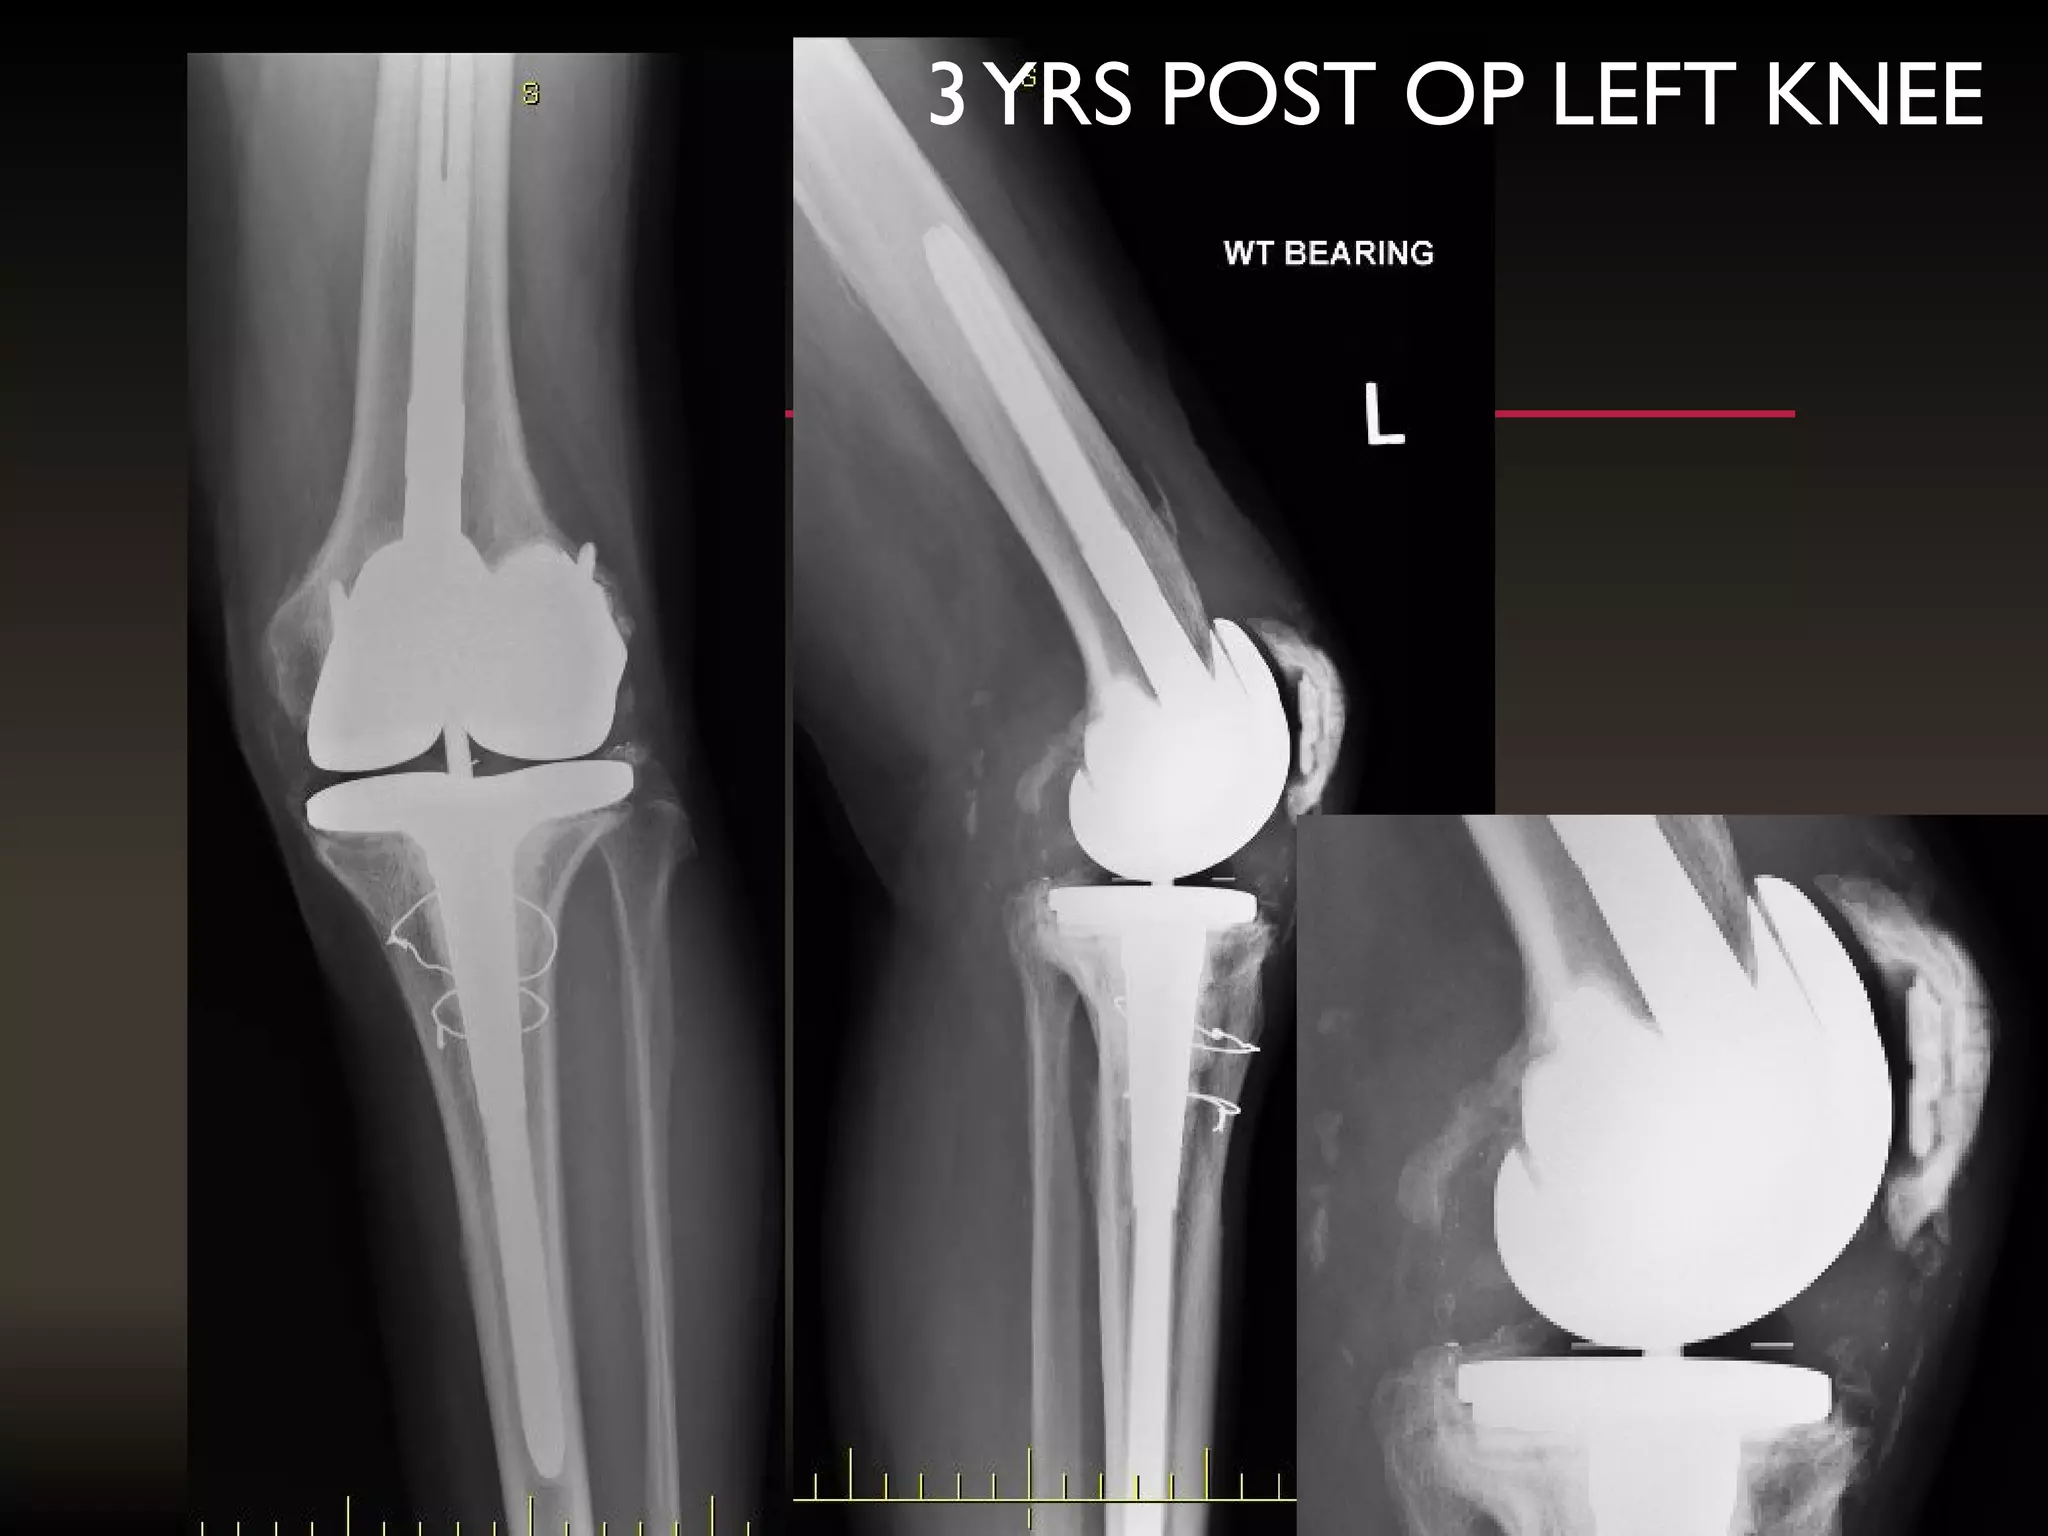

3YRS POST OP LEFT KNEE

AN INFECTEDTKR REFERRED AFTER8 MONTHS WITH A SPACER

3YRS POST OPLEFT KNEE